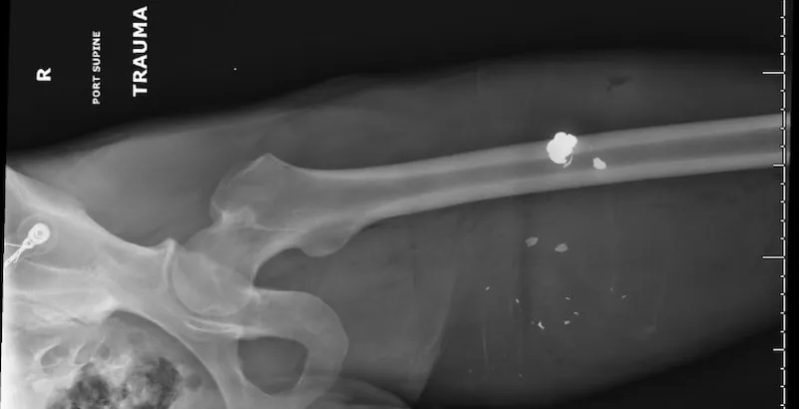

Aug 12, 2025

Lead it Be?

By: Madison Watts, MD and Anna Dulaney, PharmD, DABAT